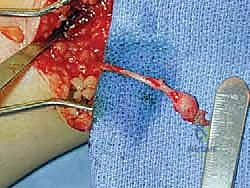

* "Here, you can see a small, nonpainful bulb neuroma from a superior peroneal nerve, buried in muscle (FIG 3). While this specific image shows the superior peroneal, the principle of identifying the nerve and its neuroma is the same for the sural. Our goal is to resect this bulb and bury the healthy proximal end."

Bulb neuroma: a small thickening on the end of the nerve; usually causes little pain ( FIG 4 )

FIG 4 • Simple bulb neuroma after sural nerve resection.